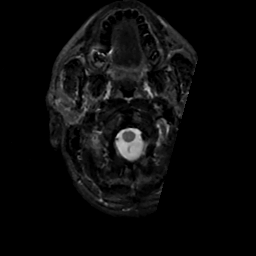

MR Study #14, June 2, 1991 -- Slice #1

[Home][Help][Clinical][Tour 1][Tour 2] Slice 1